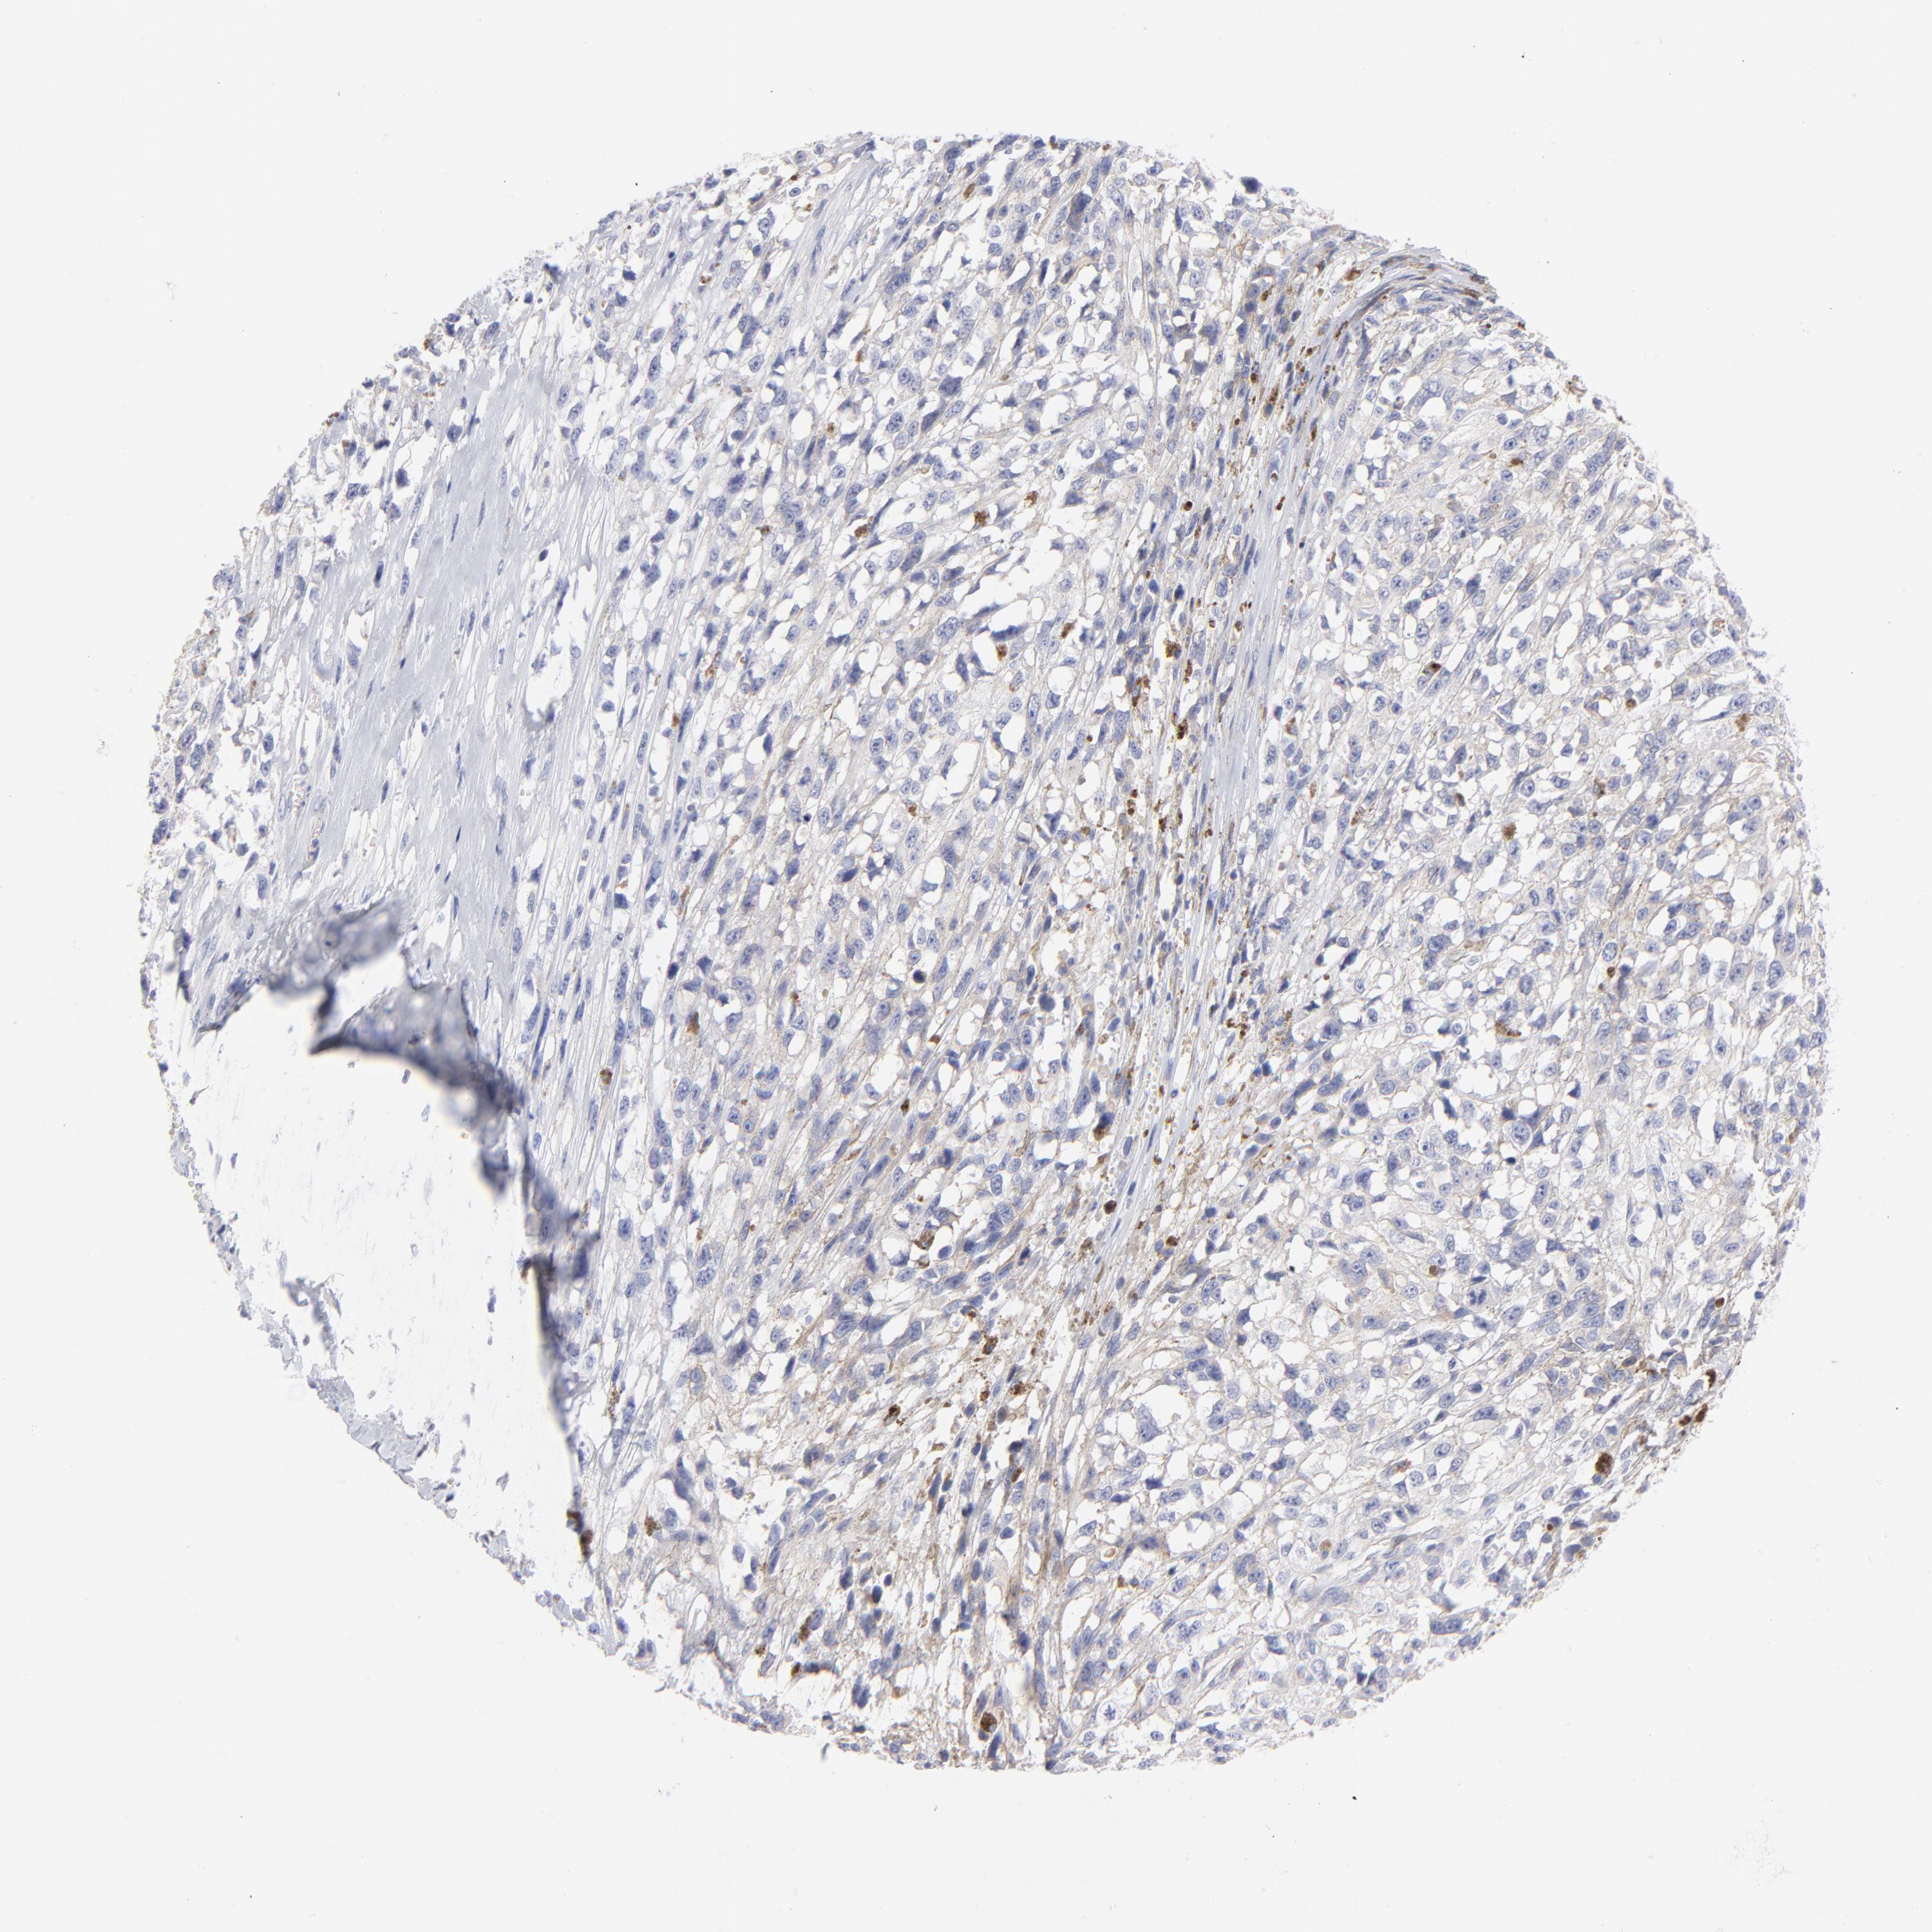

MELANOMA - Protein expressioni

A mouse-over function shows sample information and annotation data. Click on an image to view it in a full screen mode. Samples can be filtered based on level of antibody staining by selecting one or several of the following categories: high, medium, low and not detected. The assay and annotation is described here.

Note that samples used for immunohistochemistry by the Human Protein Atlas do not correspond to samples in the TCGA dataset.

Antibody stainingi

Antibody staining in the annotated cell types in the current human tissue is reported as not detected, low, medium, or high, based on conventional immunohistochemistry profiling in selected tissues. This score is based on the combination of the staining intensity and fraction of stained cells.

Each image is clickable and will lead to virtual microscopy that enables deeper exploration of all samples and also displays staining intensity scores, fraction scores and subcellular localization as well as patient and tissue information for each sample.

HPA041264

HPA041271

CAB000002

CAB003761

CAB013531

Staining

High

Medium

Low

Not detected

Intensity

Strong

Moderate

Weak

Negative

Quantity

>75%

75%-25%

<25%

None

Location

Nuclear

Cytoplasmic/membranous

Cytoplasmic/membranous,nuclear

Malignant melanoma, NOS

Malignant melanoma, Metastatic site